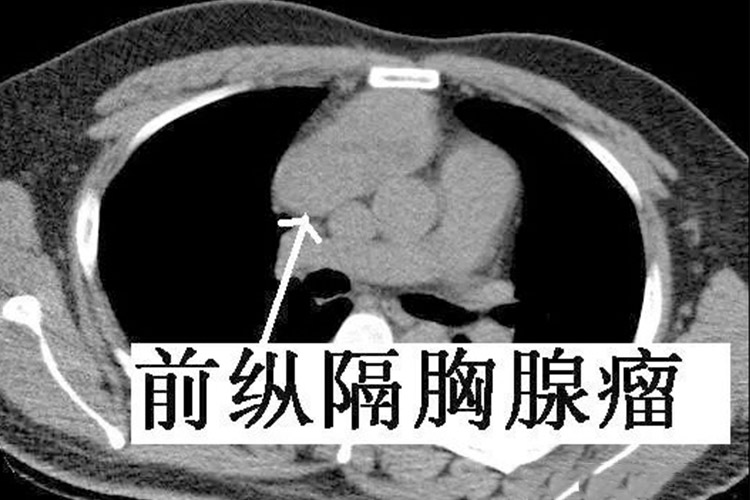

前纵隔胸腺瘤在胸内的血管前间隙,即为前纵膈区域内的胸腺瘤,具体范围上缘为上纵膈,旁边是胸膜,前缘为胸骨,后缘是心包和大血管。因此通过影像学检查可以发现位于血管前纵膈有个肿块,前贴胸骨,而后紧邻大动脉,就属于前纵隔胸腺瘤。